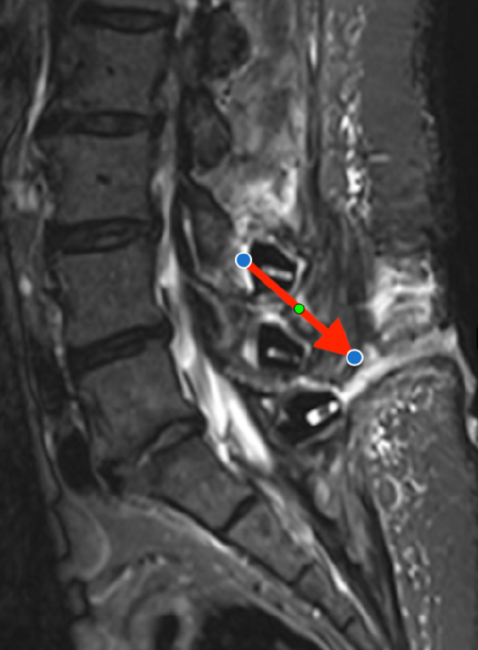

The referring physician performed microbiological samplings of the granuloma-like lesion, all of which were sterile. The CRP level was 2 mg/L, and the procalcitonin value was less than 0.2 ng/L. Contrast-enhanced lumbar spine MRI demonstrated enhancement around the posterior spinous process at the L5-S1 level as well as a fistulization of the device from the L5-S1 space to skin. However, the patient had no signs or symptoms. At the cutaneous level, the tissue had a consistency that was soft, non-exuding, and tearing, but it was neither liquid nor bloody.

MRI with gadolinium contrast is the best method for detecting postoperative spine infection. MRI findings associated with infection include fluid collections with rim enhancement and ascending epidural collections.24,25 The 2 cases discussed in the current report exhibited no clinical or paraclinical findings of infection. Fistulization between the skin and device was clearly shown on MRI. The granuloma-like skin lesions in these 2 cases were suggestive of fistulization such as can occur after abdominal surgery.